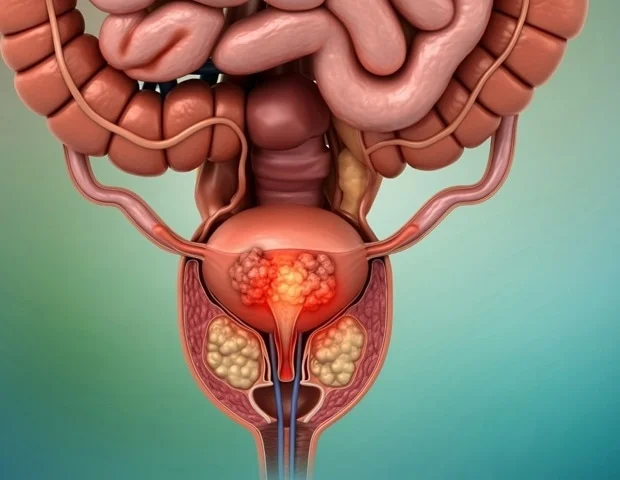

בדיקת סרטן הערמונית משתווה לטובה לסקר לסרטן השד בזיהוי סוגי סרטן משמעותיים, הפחתת תמותה והימנעות מנזקים מיותרים, אומר מחקר חדש.